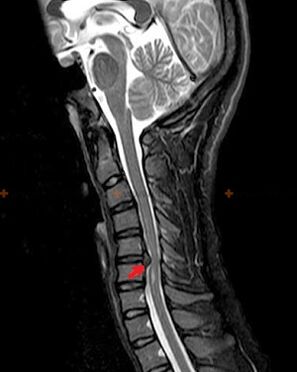

Diagnostica e segni radiografici

L'osteocondrosi è una diagnosi radiografica, poiché un quadro clinico dettagliato è presente solo al momento della riacutizzazione, mentre quando una persona è in completo benessere soggettivo possono verificarsi cambiamenti a livello della colonna vertebrale. Senza un esame radiografico si può solo parlare di sospetto di osteocondrosi, poiché sintomi simili possono essere causati anche da altre malattie (miosite, neoplasia vertebrale, ecc.).

Per diagnosticare l'osteocondrosi vengono utilizzati i seguenti metodi di esame: radiografia (preferibilmente con test funzionali), MSCT e MRI. Quest'ultimo studio è il più preferibile in quanto consente una visualizzazione molto chiara dello stato delle strutture intervertebrali.

I segni radiografici dell'osteocondrosi includono i seguenti cambiamenti nella colonna vertebrale:

- Altezza ridotta dei dischi intervertebrali.

- Presenza di escrescenze ossee marginali.

- Violazione della posizione delle vertebre l'una rispetto all'altra.

- Deformazioni dei corpi e degli archi vertebrali, ecc.

La presenza dei cambiamenti sopra descritti, così come i cambiamenti nella struttura del disco intervertebrale rilevati mediante MSCT e MRI, servono come segni affidabili della presenza di osteocondrosi.